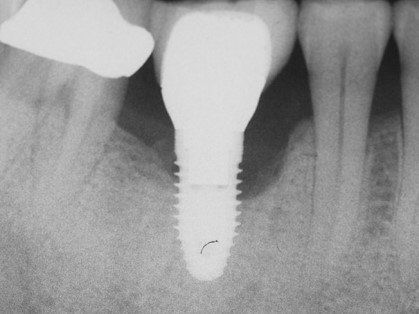

Решающее значение в диагностике периимплантита и его степени принадлежит рентгенологическим исследованиям: прицельной дентальной рентгенографии, ортопантомографии и 3-мерной дентальной компьютерной томографии, с помощью которых выявляется резорбция костной ткани. Вспомогательную роль играют лабораторные исследования – микроскопическое, бактериологическое, морфологическое, ПЦР, биохимическое, рН-метрия ротовой жидкости.

| Периимплантит | 1. Кровоточивость появляется в области периимплантной десны, возникает боль в области имплантата в покое и при жевании. 2. Наблюдается инфильтрат в месте имплантата, в зависимости от стадии периимплантита: в области краевой десны или ближе к переходной складке. 3. В дальнейшем формируется абсцесс и открывается свищевой ход. 4. На ренгенограмме наблюдается характерная кратерообразная деструкция кости в области имплантата. |

Рентгенография. Позволяет отличить периимплантный мукозит от периимплантита: при мукозите на рентгенограмме нет патологических изменений вокруг имплантата; при периимплантите видно убыль кости. Также рентген помогает определить глубину зондирования и увидеть плохое прилегание элементов протеза [14] .